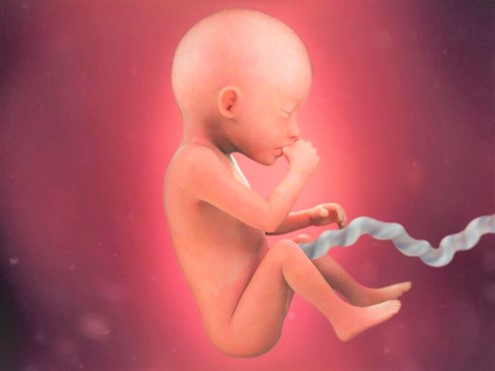

Развитие зародыша на 12 неделе: визуальный обзор